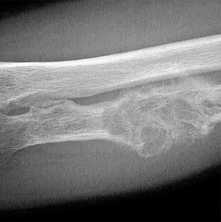

- Деструкция с «разъеданием» костной структуры на рентгенограммах выглядит как дефект - «дырка», такой вариант метастазирования называют остеолитическим, что буквально означает «съеденная кость».

- При утолщении кости за счёт опухоли рентгенограмма выявляет «плюс ткань», тогда говорят об остеопластическом метастазировании.

- Как правило, у больного встречаются оба вида метастазов с превалированием одного из вариантов, в большинстве случаев остеолитического.